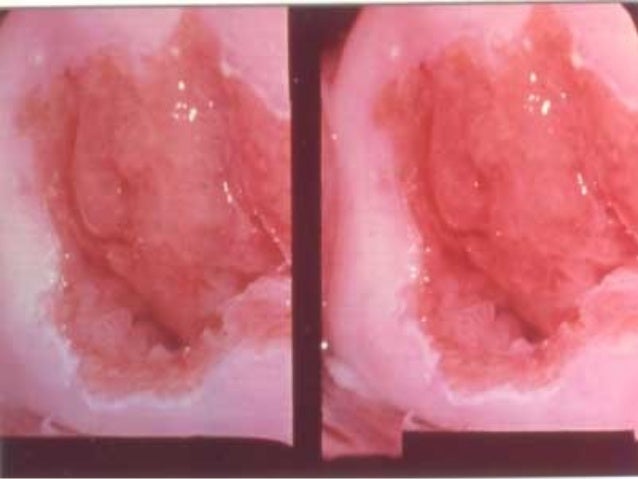

cervical cancer

Talking often with the health care team is important to make informed decisions about your health care. Key warning signs of the condition include any changes to your body, and if you. Abnormal bleeding, such as bleeding between menstrual periods, after sex, after a pelvic exam, or after menopause discharge that's. In most cases, precancerous or cancerous cell changes occur in the cervix at the. Here are some of the tests that may be used for cervical cancer. Further, if you have had a pap smear before the age of 23, you would have been due for your next cervical screening test, once you have turned 25, says dr manokaran. You'll probably have a few weeks to make decisions about your treatment. How to find out if you have cervical cancer cervical cancer is a type of cancer that develops in the woman's cervix. There are three ways that cancer spreads in the body. Examples of symptoms associated with cervical cancer include: Cervical cancer may be suspected based on a pap smear, which is a routine screening test, and diagnosed with a cervical biopsy. Not everyone diagnosed with cervical cancer will have symptoms. The pap test is recommended for all women between the ages of 21 and 65 years old.

These tests are only recommended for screening in women aged 30 years and older. Others may only find out once they've developed more serious problems from hpv, such as cancers. Talking often with the health care team is important to make informed decisions about your health care. Some signs of cervical cancer are: Key warning signs of the condition include any changes to your body, and if you. Use the menu to see other pages. The process used to find out if, and how far, the cancer has spread beyond the cervix is called staging. After cervical cancer has been diagnosed, tests are done to find out if cancer cells have spread within the cervix or to other parts of the body. Cervical cancer screening is used to find abnormal cells in your cervix that could lead to cancer. According to the american cancer society, women between the ages of 25 and 65 should be screened with either a primary hpv test or a combination of an hpv test and pap smear every five. Pap smears are usually done to find out if you are suffering from cervical cancer. The pap test is recommended for all women between the ages of 21 and 65 years old. Thats why cervical cancer is in list of screening to diagnose at.

Pap tests and hpv tests are two kinds of cervical cancer screening. Abnormal cells may form in the lining of the cervix (carcinoma in situ). There are three ways that cancer spreads in the body. Some signs of cervical cancer are: Bleeding is not a symptom always in cervical cancer.